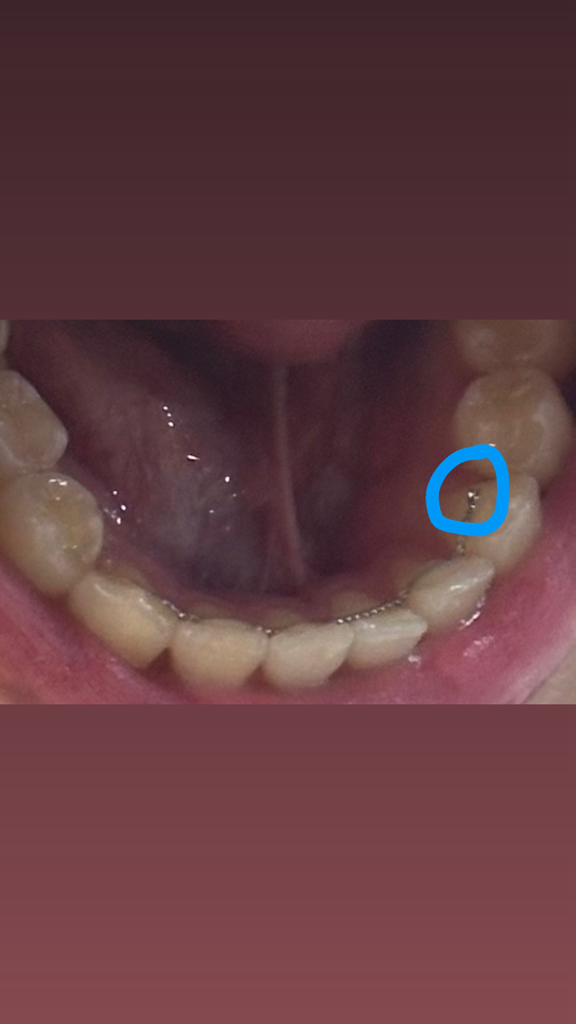

사진에서 아직은 끝부분망 살짝 떨어진거 같네요

치과로 가셔서 재부착하는 걸 추천합니다.

방치되면은 더 탈락이 되면서...

혀가 찔리기 시작하거나, 재부착이 어려운 정도로 변형이 될 기능성이 커집니다.

지금 상태는 손쉽게 수리가 가능합니다.